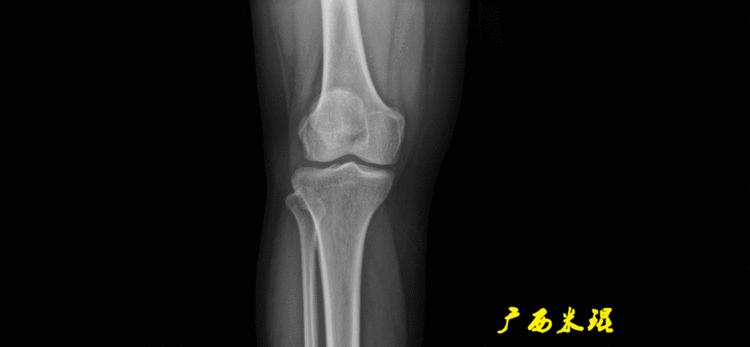

股骨远端外侧角(mLDFA):股骨内外侧髁远端切线(关节线)与股骨头和膝关节中心的连线(机械轴)两者之间形成的外侧夹角,正常为87°±3°。

胫骨近端内侧角(mMPTA):胫骨内外侧平台切线(关节线)与股骨头和膝关节中心的连线(机械轴)两者之间形成的内侧夹角,正常为87°±3°。

解剖股胫角(aFTA):股骨干下段轴线(解剖轴)与胫骨上段轴线(解剖轴)在膝关节所形成的夹角,正常为174°±1°。膝关节OA的畸形常常由于一侧软组织及关节的过度磨损所致,临床多为内侧磨损过度,因此表现为轻度膝内翻畸形,X线表现为解剖股胫角小于174°,而胫骨角正常。

解剖股骨远端外侧角(aLDFA):股骨干下段轴线(解剖轴)与股骨内外侧髁远端切线(关节线)在膝关节外侧所形成的夹角,正常为81°±2°。大多数膝外翻患者的畸形发生于股骨下端,表现为股骨远端外侧角小于正常值。

解剖胫骨近端内侧角(aMPTA):胫骨内外侧平台切线(关节线)与胫骨解剖轴两者之间形成的内侧夹角,正常为87°±3°。由于胫骨解剖轴与机械轴几乎一致,所以一般解剖胫骨近端内侧角与机械胫骨近端内侧角一致。

解剖胫骨近端外侧角(也叫aMPTA):胫骨干上段轴线与胫骨平台切线(关节线)在膝关节外侧所形成的夹角,常称为胫骨角,正常为87°±3°。大多数膝内翻患者的畸形发生于胫骨上端,表现为胫骨角大于90°。严重的膝内翻畸形发生在整个下肢,股骨干及胫骨干都有可能形成向内弯曲的弧形。

胫骨股骨关节线夹角(JLCA):胫骨近端关节线与股骨远端关节线之间的夹角,正常生理状态下几乎为0°。当JLCA>2°时提示异常,通常为韧带松弛或者软度磨损丢失所致。

最常见的下肢畸形发生于冠状面,即膝内外翻畸形,冠状面的对线异常通过应用“对线异常检验”进行分析,机械轴的偏移(MAD)表现为对线异常。

膝内翻是指下肢力线通过膝关节中心点内侧,距中点2mm以上,偏内超过15mm为显著膝内翻。膝外翻是指下肢力线通过膝关节中心点外侧,距中点2mm以上,偏外超过10mm为显著膝外翻。